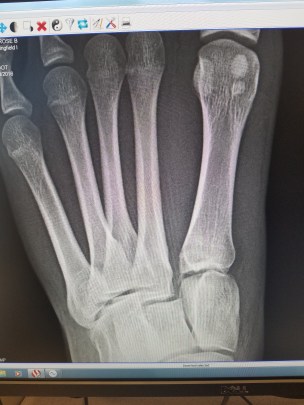

Mia Rose had sustained a lisfranc injury. She ordered a weight bearing x-ray, meaning that Mia Rose had to stand on her injured foot while they took the x-ray (not fun). Ten minutes later the doctor showed us the x-ray you see here and explained that it indicated an unstable lisfranc injury with a 2 mm separation and that surgery was required. She said that the lisfranc ligament was torn which was what allowed the bones to dislocate and that in order for the ligament to heal the bones had to be put back in perfect alignment and kept that way with screws. This was devastating news for Mia Rose who was getting ready to head into her competition season with the expectation of a great season.